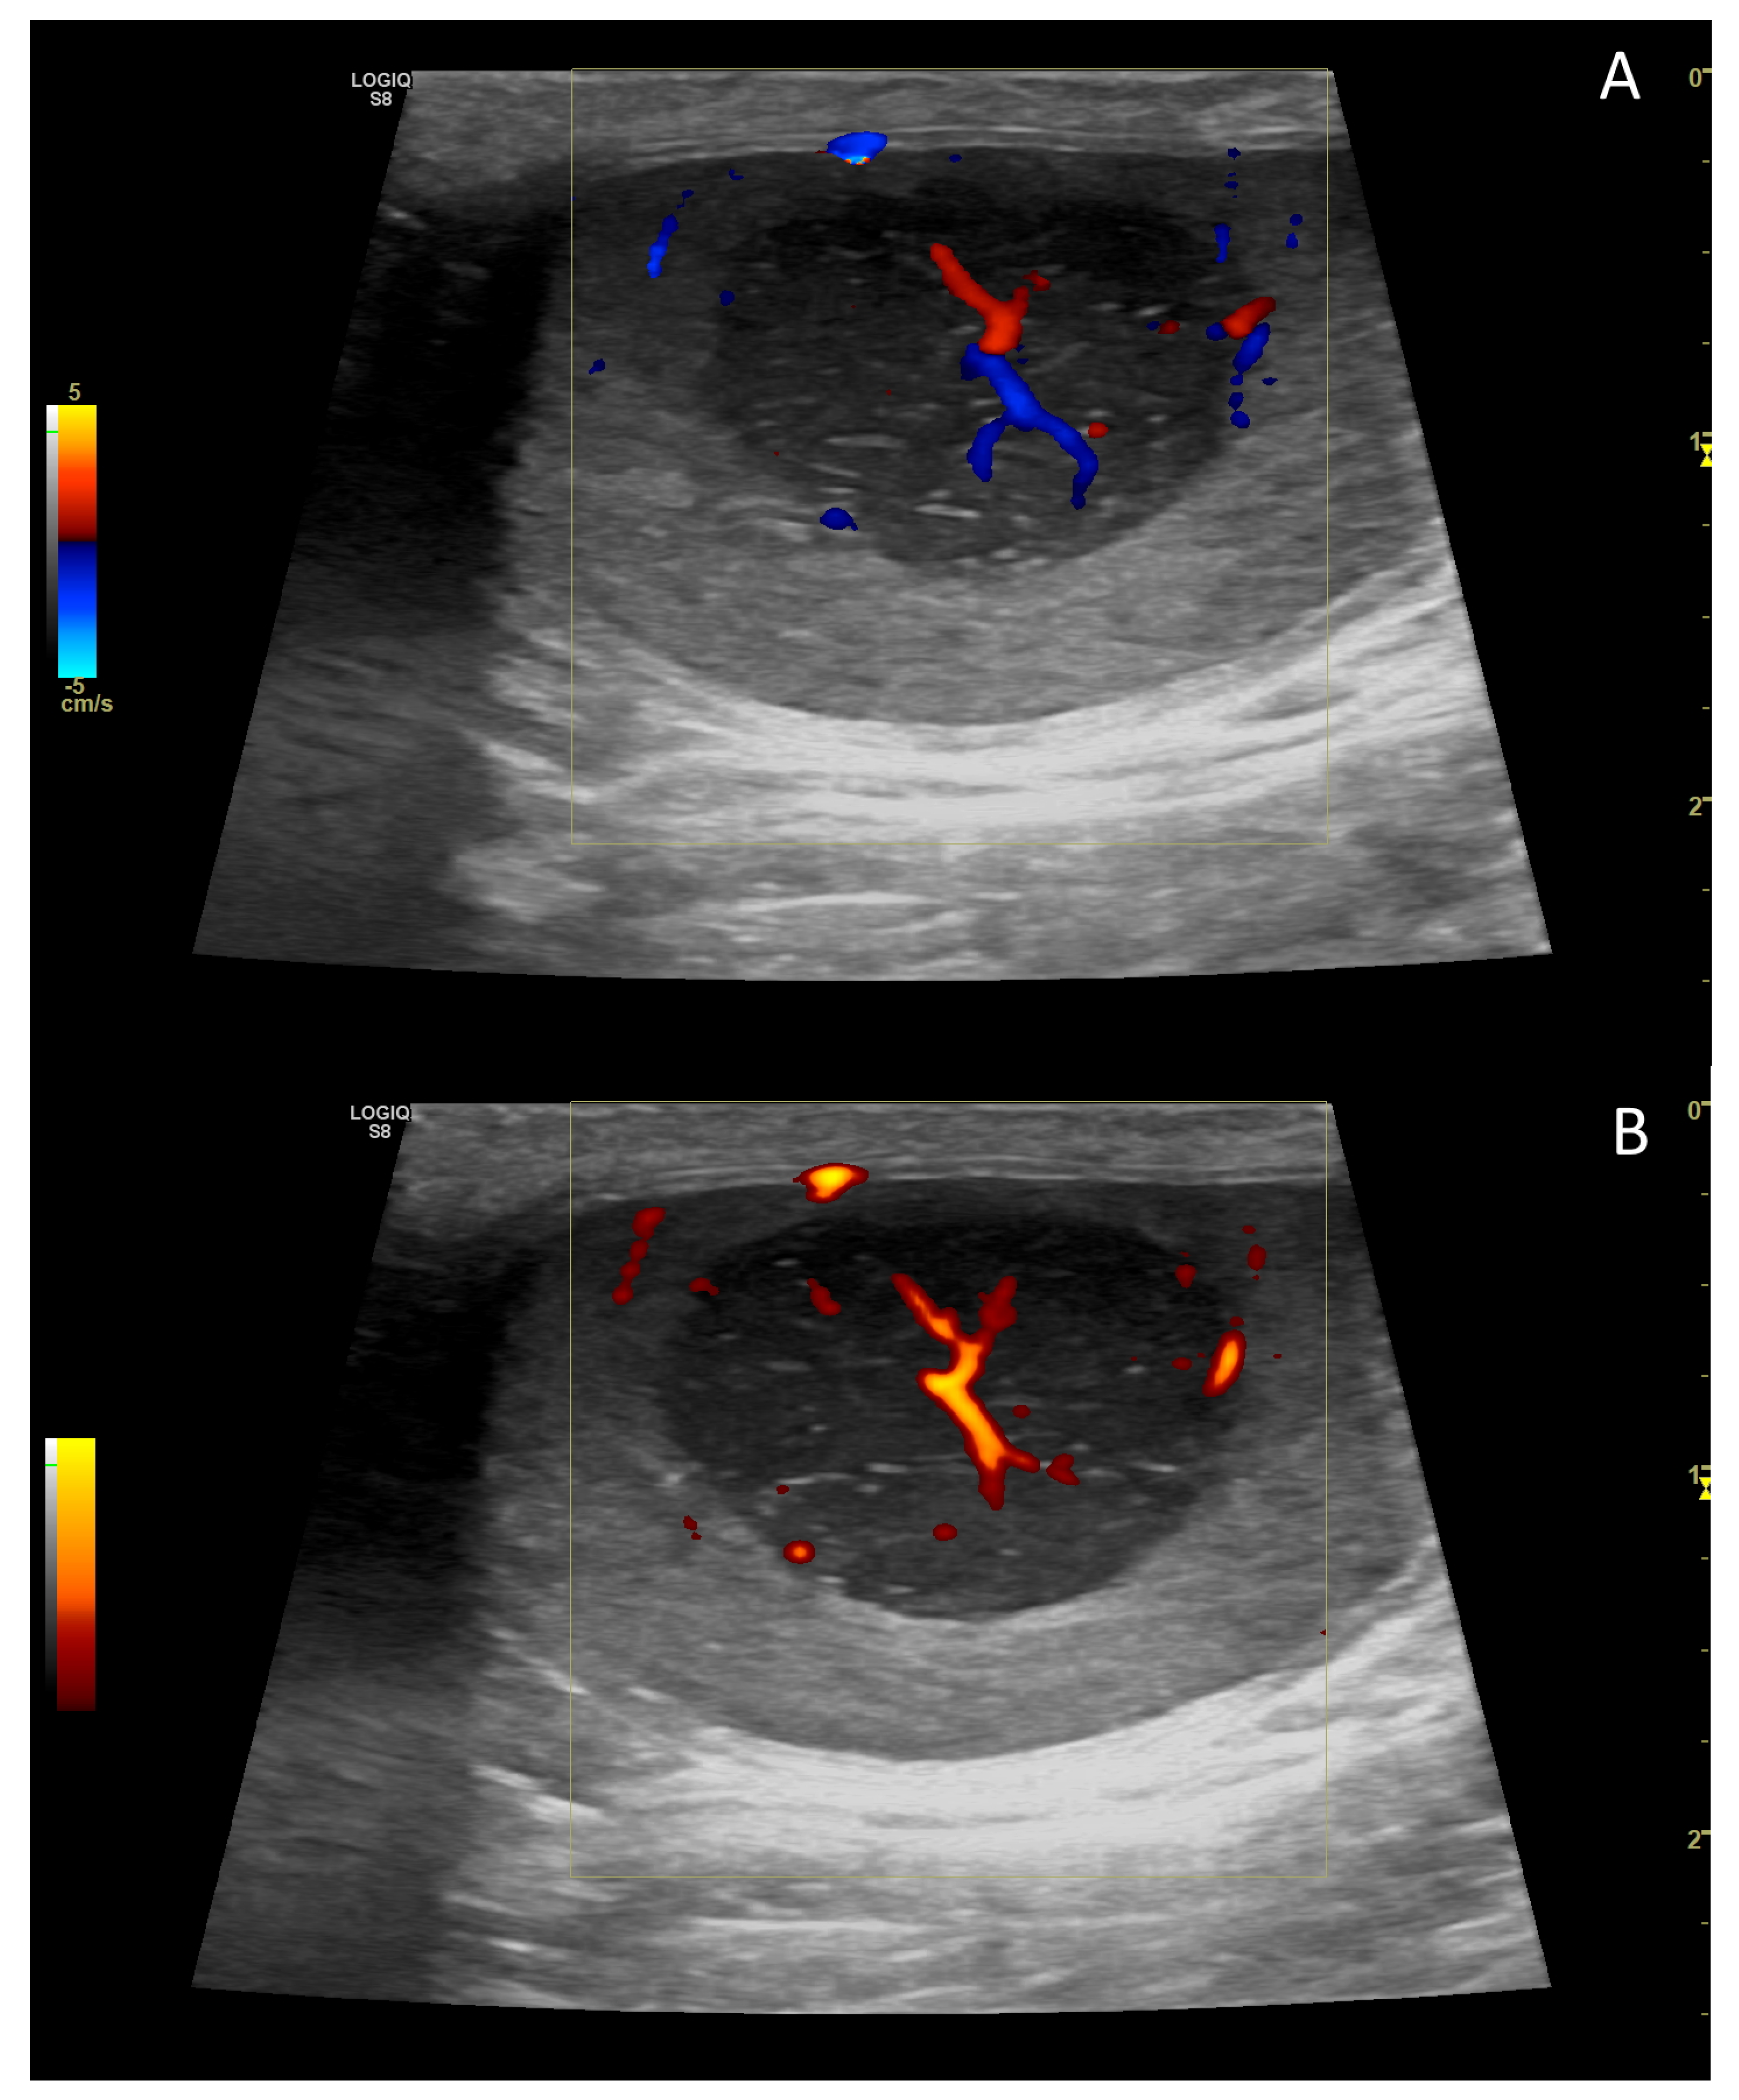

4. Colour Doppler and Power Doppler

4.2. Normal Findings

4.4. Abnormal Findings